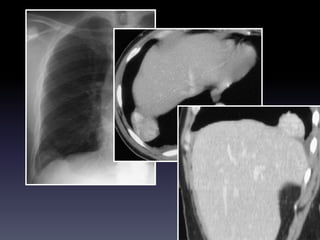

U MAØNG PHOÅI

U aùc tính maøng phoåi

PA,

decubitus

U xô laønh tính maøng

phoåi